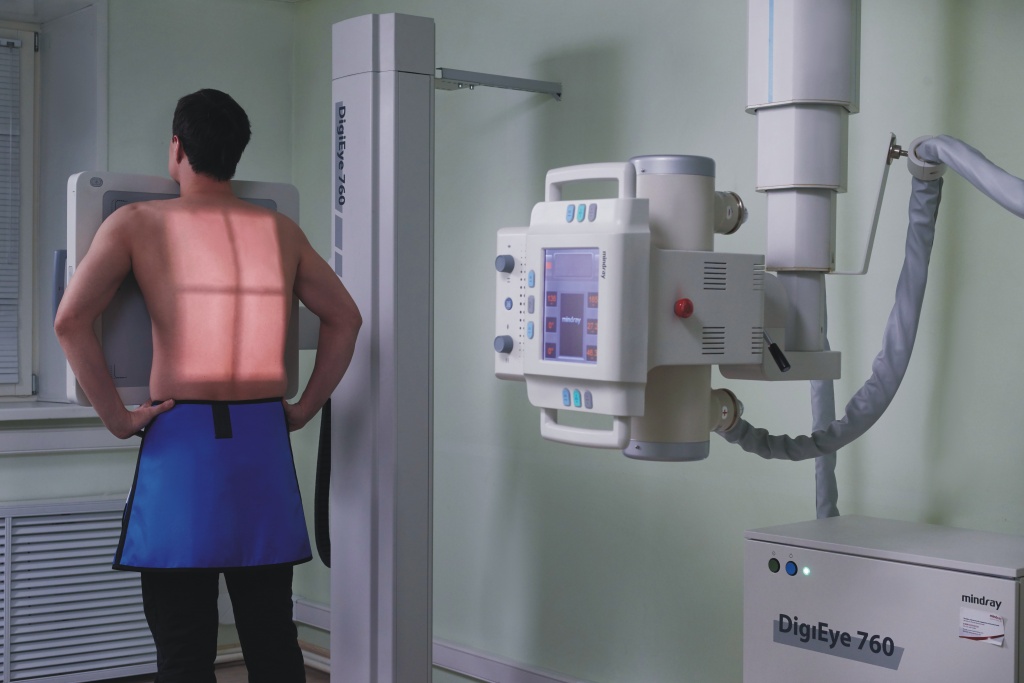

Влияние излучения при флюорографии: что нужно знать?